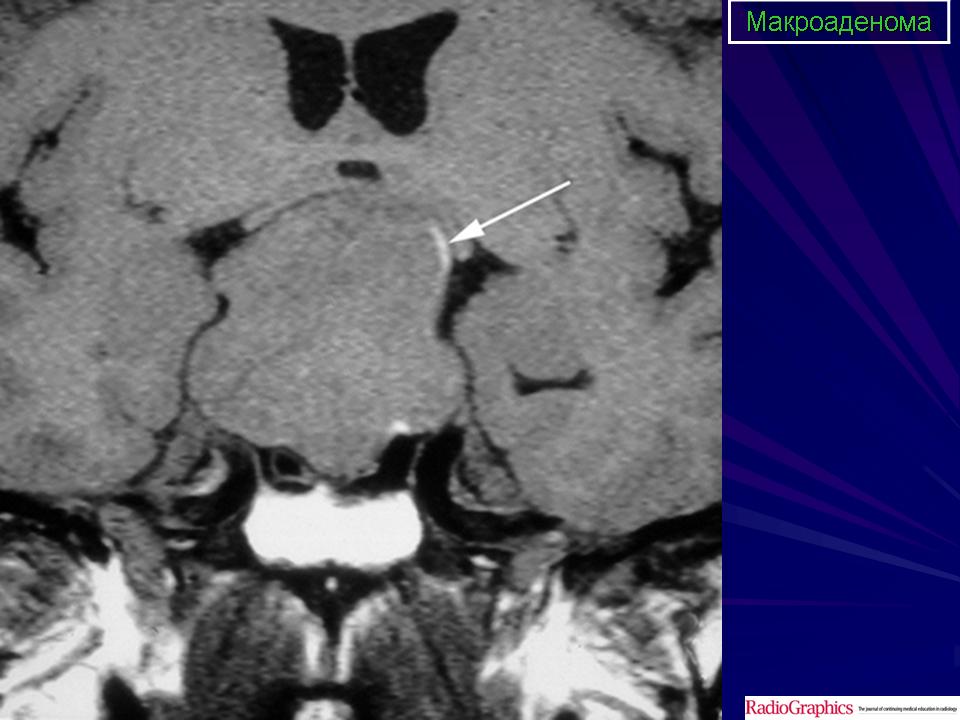

ГМ. Аденома гипофиза 1. +

Аденома гипофиза.